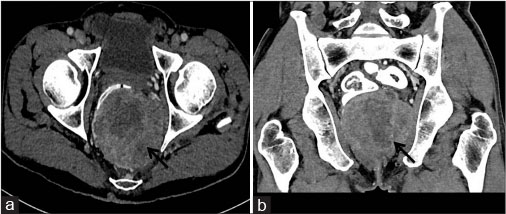

A 63-year-old-male patient presented with on and off constipation for the past 3 months. The patient was chronic smoker for 20 years. Per rectal examination revealed solitary palpable mass along posterior rectal wall extending from 4 to 8 o’clock position. Patient’s blood counts, viral markers, and chest X-ray were normal. With a suspicion of rectal malignancy, triphasic contrast-enhanced CT abdomen was performed. CECT revealed heterogeneous predominantly exophytic mass lesion abutting the rectum [Figure 1]. On histopathological examination, the specimen revealed fibrocollagenous cores with a cellular spindle cell tumor comprising of spindle cell. On immunohistochemistry, tumor cells were strongly positive for CD34 and CD117 [Figure 2]. Postimatinib therapy, the tumor showed a significant reduction in size, attenuation, and internal neovascularity [Figure 3].

| Figure. 3 (a and b) Posttreatment imaging. Axial and coronal reformatted computed tomography images showing significant reduction in size, attenuation, and enhancement of the rectal gastrointestinal stromal tumor suggestive of partial response